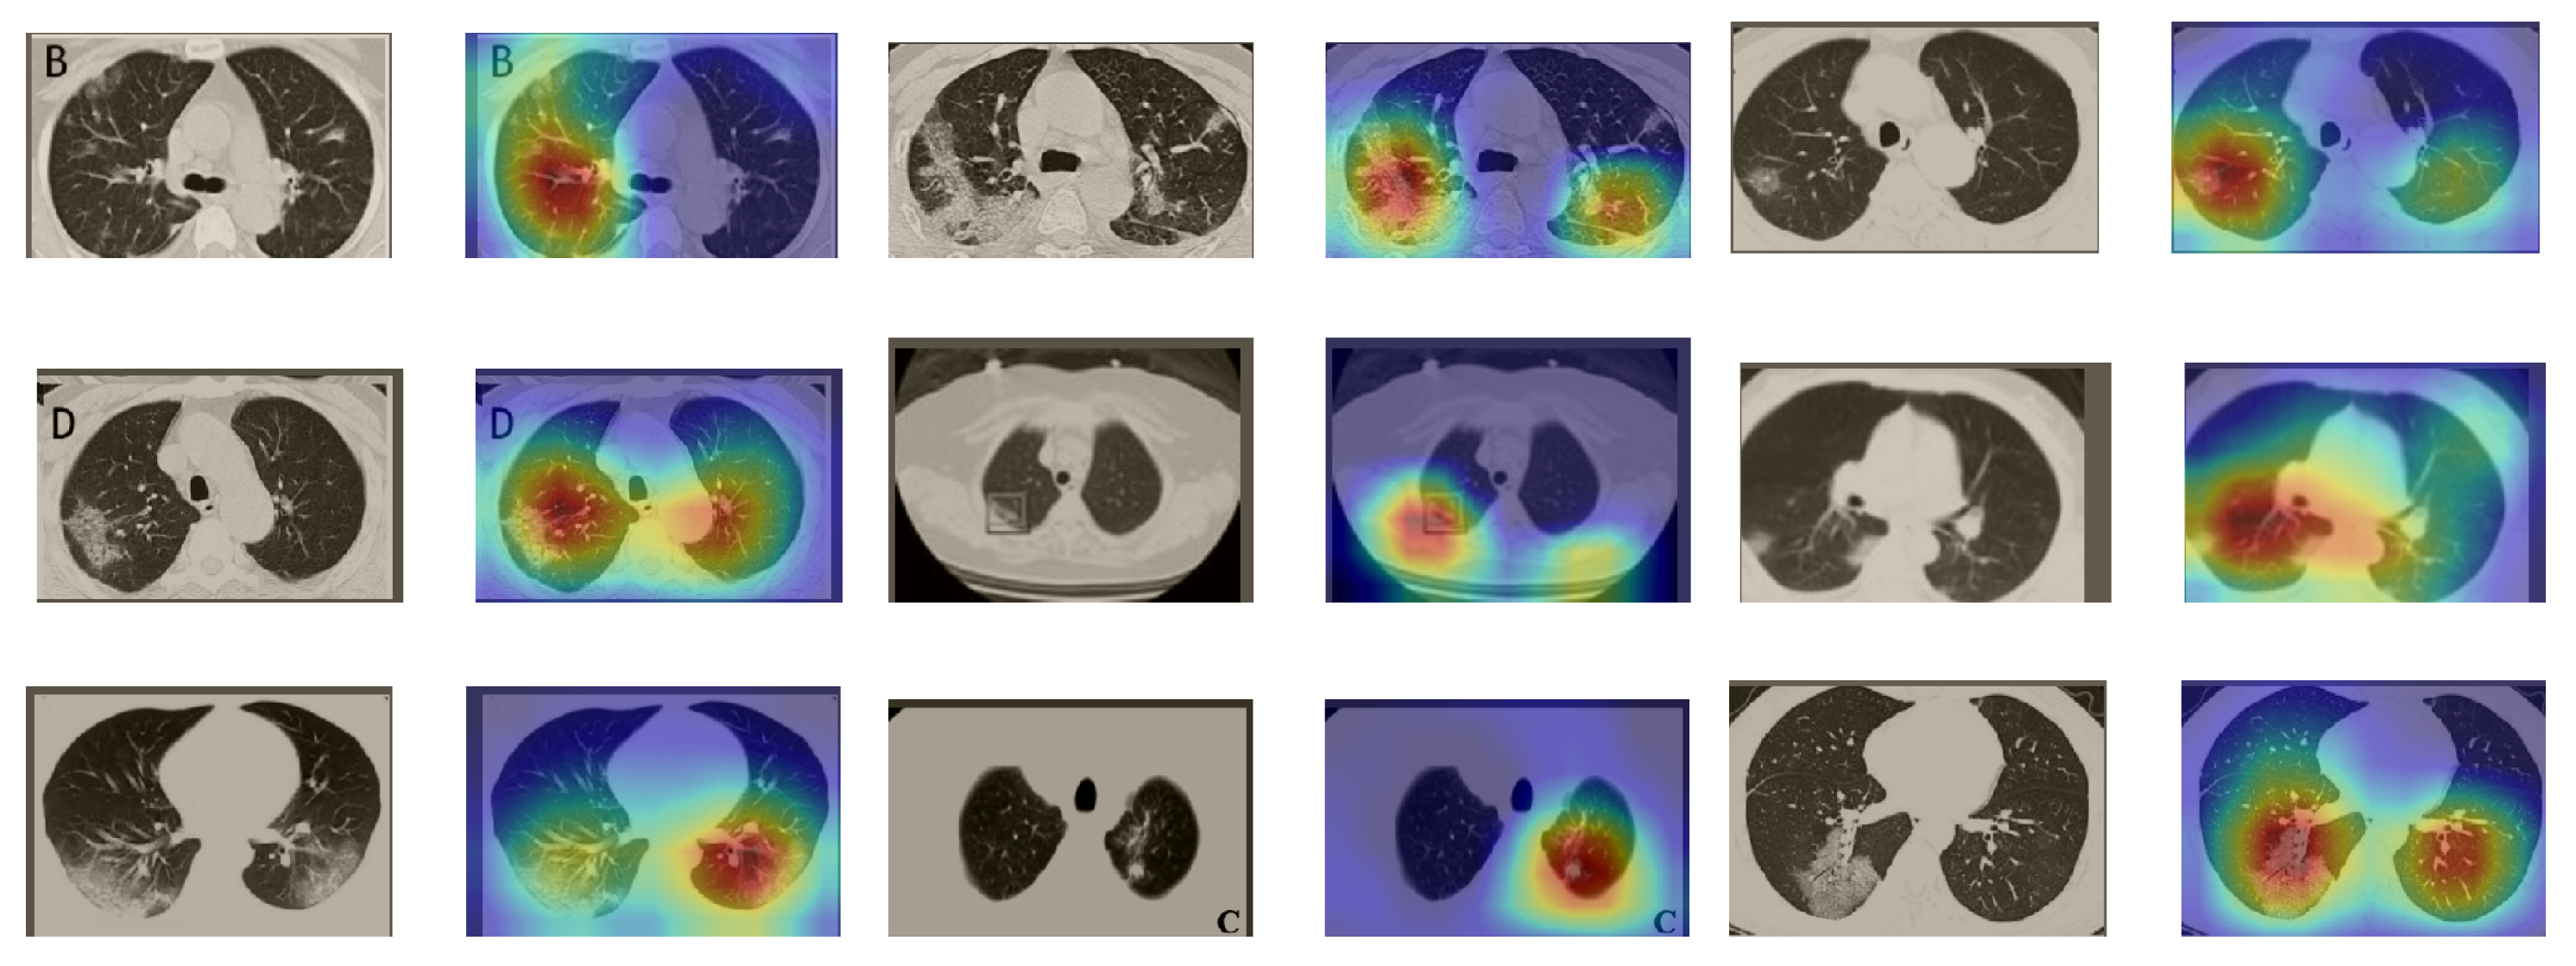

A wide variety of typical and atypical chest CT abnormalities of COVID-19 patients have been reported in various studies [61,62]. In order to investigate the ability of our models to identify COVID-19 cases outside the considered datasets and localize their CT findings, we tested our models on external CT images extracted from these two publications, as they feature typical findings of COVID-19 pneumonia marked by specialists. To make sure that none of the extracted images were unintentionally included in our datasets, specifically the COVID19-CT dataset, we used the model trained on the SARS-CoV-2 dataset. First, the InceptionV3 model was used to classify the extracted CT images. The model was able to correctly classify the given CT images as COVID-19. Second, in order to interpret the model’s generalization capabilities, we applied the Grad-CAM technique to visualize the regions of abnormalities that are considered. By assessing the different CT images in Figure 15, we can see that the model accurately localizes the disease-related regions. Even more interesting is the fact that the model ignores any specific marks in the images such as the letters and only localizes the COVID-19-related regions. These further experiments prove the success of our models to learn distinguishable visual features related to COVID-19, and to correctly classify CT images outside the datasets on which they are trained and tested.

Figure 15.

Examples of CT images taken from these two publications [61,62]. The CT images were correctly classified as COVID-19 cases, and the abnormal regions are accurately detected as in the localization maps.

In order to investigate the capacities of the different models to accurately localize identical or similar important regions, we employed the model with the lowest accuracy, i.e., SqueezeNet, which was fine-tuned on the SARS-COV-2 dataset to classify the unseen CT images taken from [61,62]. Moreover, we provide the Grad-CAM localization maps for a direct comparison. Figure 16 illustrates CT images, which represent the first two rows in Figure 15, and their corresponding localization maps. For most of the cases, both models looked exactly at similar regions representing the COVID-19 manifestations. However, for some images, SqueezeNet looked at irrelevant regions, such as the top left corner.

Figure 16.

Grad-CAM visualizations for the same CT images in the first two rows of Figure 15. The CT images were correctly identified by SqueezeNet as COVID-19 cases with relevant localization of the disease-related regions.

Although we trained our models using CT images where both lungs are visible in the scans, we tested them on some external CT scans where only one lung is visible. The CT scans were extracted from the paper [61] and show different CT manifestations of COVID-19 marked by red squares or white arrows. Our models were able to classify them correctly as COVID-19 cases. Intriguingly, when applying Grad-CAM we can see from Figure 17 that all regions of abnormalities are accurately localized. This also proves the potential of our models to detect COVID-19 abnormalities in CT images outside the dataset used for training.

Figure 17.

Example of annotated CT scans with different manifestations of COVID-19 taken from [61], and their corresponding localization maps. Our models were able to identify them as COVID-19 cases and accurately localize their COVID-19-associated regions.

For a comprehensive analysis of our visual explanations, we include some cases wherein the models failed to localize the exact COVID-19-associated regions. Figure 18 illustrates examples of CT scans that were correctly identified by our models as COVID-19 cases, but with which our models failed to localize the most relevant regions associated with COVID-19 as marked in some CT images. These failure behaviors can be attributed in some cases to focusing on similar findings or subtle density of manifestations found in the early days of infection. Nevertheless, in some cases the models only localized the findings in one lung and failed to highlight the disease-related regions in the other lung.

Figure 18.

CT scans and their Grad-CAM localization maps showing cases in which the model failed to localize the most relevant COVID-19 regions.